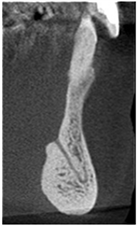

To select the area of interest, the distance between the mesial extremity of each mental foramen was measured, and half of this distance guided the average tomographic image. From this section, five parasagittal tomographic sections were evaluated for each side. The section that presented the greatest clarity of the genial plexus was chosen to perform the measurements (Figure 1(A)).

Figure 1. Tomographic images, diameters and distances of the canal and plexus. (A) Parasagittal tomographic image; (B) Canal diameter; (C) Distance from the genial plexus to the cortical bone; (D) Initial parasagittal tomographic image, central incisor tooth. Source: Own Authorship. Caption: Parasagittal tomographic image measuring the length (A) canal diameter (B) and distances as follows: (L1) of the genial canal; (L2) distance from the genial plexus to the alveolar bone crest, (L3) distance from the genial plexus to the buccal cortical bone and the base of the mandible (L4) (C), initial parasagittal tomographic image (D). Figure 1 (A) Parasagittal section of the CBCT used to perform measurements. (B) Longest width of the genial canal (W). (C) longest length of the genial canal (L). (D) Shortest distance from the genial plexus to the alveolar bone crest (D1); shortest distance from the genial plexus to the buccal cortical bone (D2); shortest distance from the genial canal relative to the base of the mandible (D3).